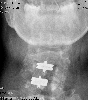

Don't ask me why my neck's tilted like that - it's exactly the way the radiologist positioned my head for the shot.